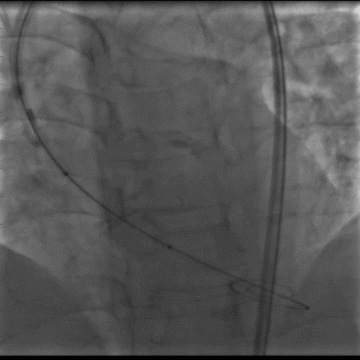

术中造影

瓣膜初始定位